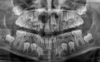

La radiographie panoramique

C'est le cliché de routine qui permet d'appréhender l'ensemble de la dentition et des structures sous-jacentes.

Il est réalisé en début de traitement pour poser le diagnostic et en cours de traitement pour contrôler le bon déroulement de celui-ci.

Nous sommes équipés pour réaliser ce cliché sur place dans notre cabinet.